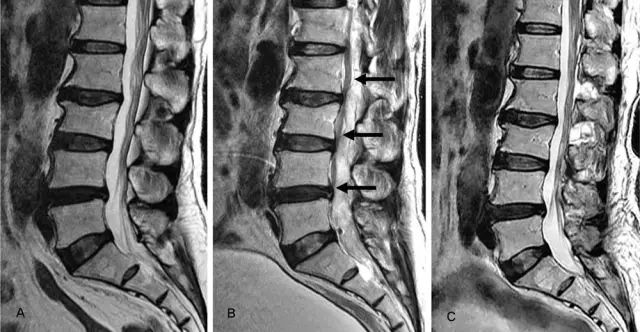

颈部磁共振显示

椎管硬膜外血肿需要行手术治疗

简单的说也就是

血管破裂压迫神经造成了开头说的症状